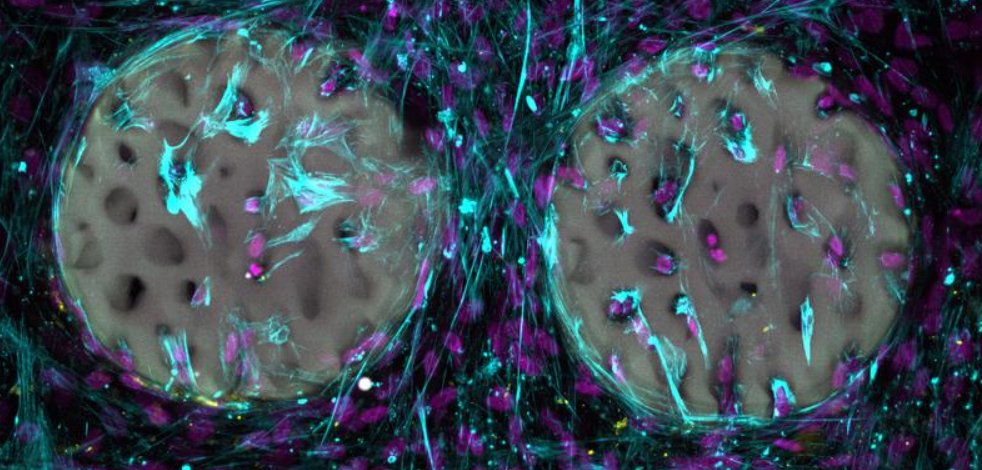

DSMZ Provides First Animal-Component-Free Cancer Cell Lines for Research

The Leibniz Institute DSMZ – German Collection of Microorganisms and Cell Cultures GmbH has successfully adapted four widely used human cancer cell lines (HELA, HL-60, K-562 and JIMT-1) to animal-component-free media. The world's most diverse cell bank collection now...